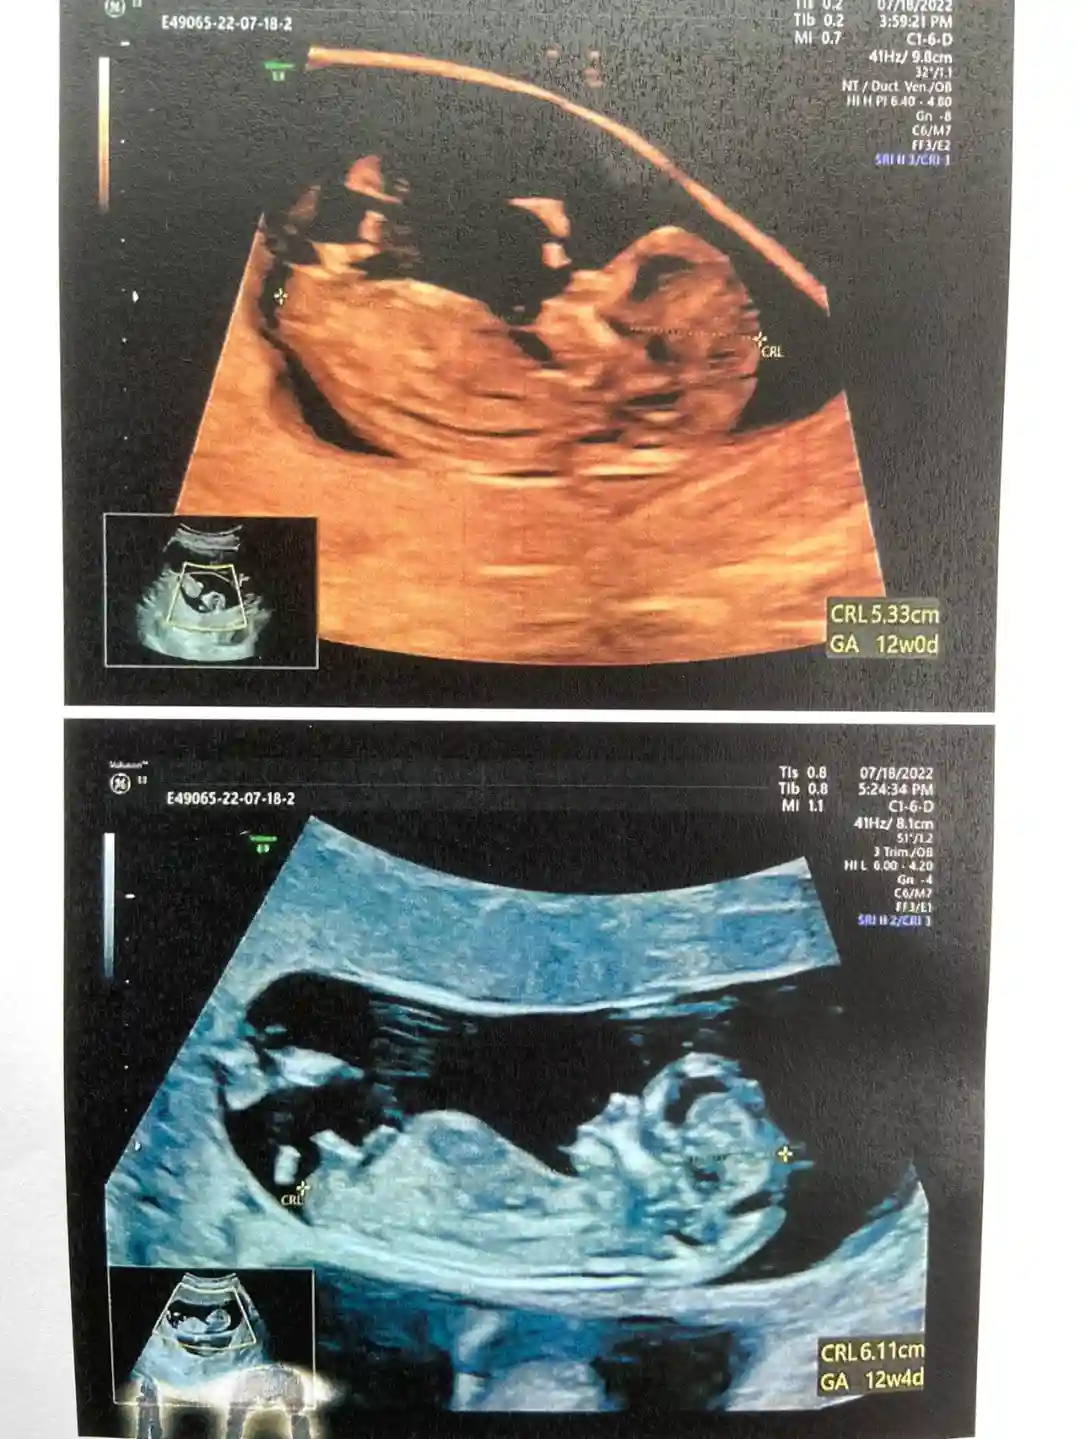

二代试管一促一移,费用3.5万左右,从2022年3月第一次进医院,到2022年7月毕业,感谢自己的坚强与坚持,感谢老公的陪伴与爱护,感谢宝宝们选我们当爸爸妈妈。对医院我整体感受都很好,非常感谢西南医院生殖科的医生和护士们,接下来我要去麻烦产科的医生护士了。

#双绒双羊 #双胎 #二代试管